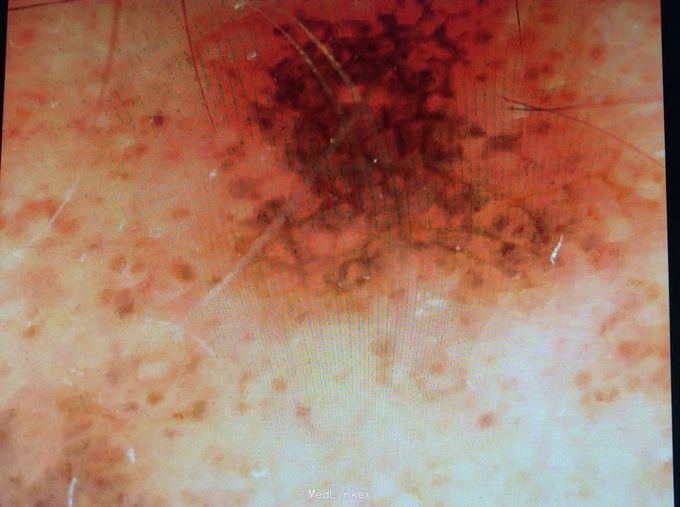

查体:颈部褐色斑片,形状不规则,边界清楚,中心可见黑色斑点,未突出皮面,无破溃。 皮肤镜下见较多色素沉着,局部融合呈团巢状。

诊断:斑痣 处理:建议手术切除,活检结果待回报。

斑痣为一扁平咖啡色斑片,其上可见平坦或隆起的斑点。与日光暴露无关,可发生于任何年龄,但很少出生时就有,通常在婴儿后期和儿童早期出现。